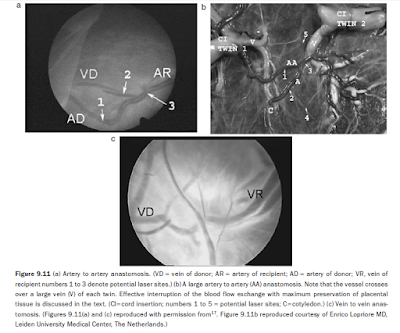

In a four-vessel cotyledon, both fetuses perfuse a common cotyledon with an artery and a vein of each. Deep anastomoses are classified as AVDR if the artery corresponds to the donor twin, or AVRD if the artery belongs to the recipient twin. The size of the anastomoses (‘hair’, small, medium, large, or very large) is also noted. Superficial anastomoses are identified as being arterioarterial (AA) or venovenous (VV) (Figures 9.11a,b), and can be easily seen running uninterrupted between the two fetal circulations. AA anastomoses are more easily detected, as they cross over veins. Superficial anastomoses may be branched or unbranched.16 Typically, the direction of flow in VV anastomoses cannot be determined endoscopically.